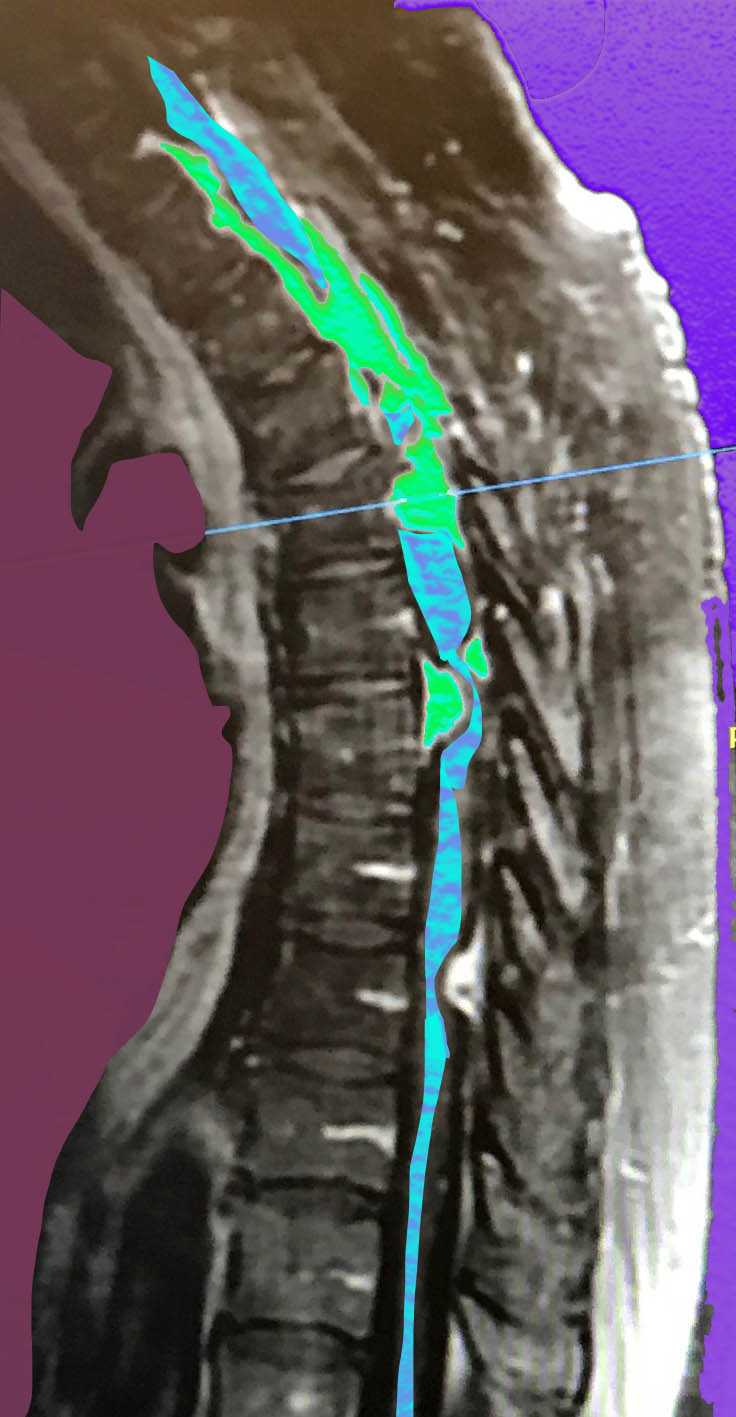

In November I had big, motherfucking spine surgery with Jen questblogging commentary and the results Naturally, I got in one or two posts – observations and kvetches – about, amongst other things, those nasty-ass wolverines who ALWAYS stop in post surgery.